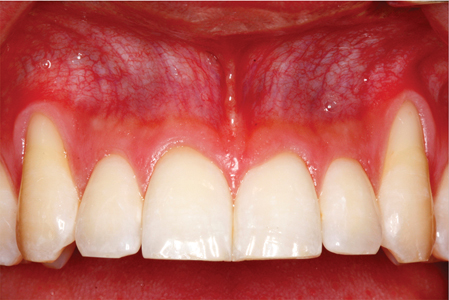

Soft Tissue Grafting To Improve Aesthetics, To Reduce Dentinal Hypersensitivity, To Improve The Prognosis Of Compromised Teeth And To Augment Edentulous Ridges Prior To The Placement Of Implants

Introduction Over the past two decades, surgeons have shown an increased interest in mucogingival procedures to rehabilitate soft tissues around both teeth and implants, in an attempt to master our shared domain of the oral apparatus.1 A variety of techniques and materials have been studied, and sufficient high-level research exists to guide us in selecting … Read more